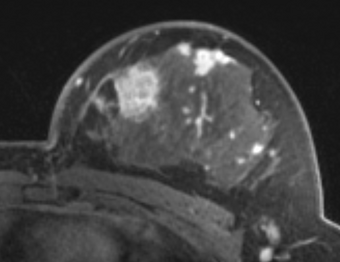

PkModeling (Pharmacokinetics Modeling) calculates quantitative parameters from Dynamic Contrast Enhanced DCE-MRI images. This module performs two operations:

- estimation of quantitative perfusion parameters from DCE MRI

- treatment response evaluation

- breast, prostate, brain DCE MRI analysis